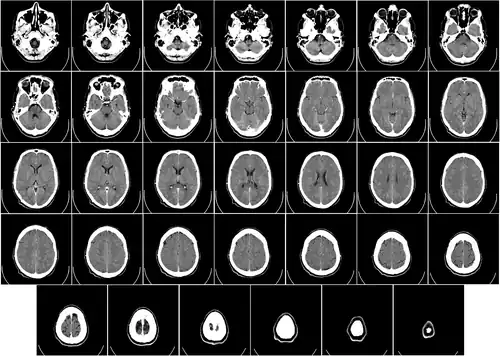

Объём мозга большинства людей находится в пределах 1250—1600 кубических сантиметров и составляет 91—95 % ёмкости черепа. В головном мозге различают пять отделов: продолговатый мозг; задний, включающий в себя мост, мозжечок и эпифиз; средний; промежуточный; и передний мозг, представленный большими полушариями. Наряду с приведённым выше делением на отделы, весь мозг разделяют на три большие части:

Половые различия

Мозг взрослого мужчины в среднем на 11—12 % тяжелее и на 10 % больше по объёму, чем женский[19][20], что соответствует разнице в массе и размерах тела у полов. Статистической разницы между соотношением размеров тела и мозга у мужчин и женщин не обнаружено[5][21]. Методы томографического сканирования позволили экспериментально зафиксировать различия в строении головного мозга женщин и мужчин[22][23]. Установлено, что мозг мужчин имеет больше связей между зонами внутри полушарий, а женский — между полушариями. Данные различия в структуре мозга были наиболее выражены при сравнении групп в возрасте от 13,14 до 17 лет. Однако с возрастом в мозге у женщин количество связей между зонами внутри полушарий возрастало, что минимизирует ранее отчётливые структурные различия между полами[23].